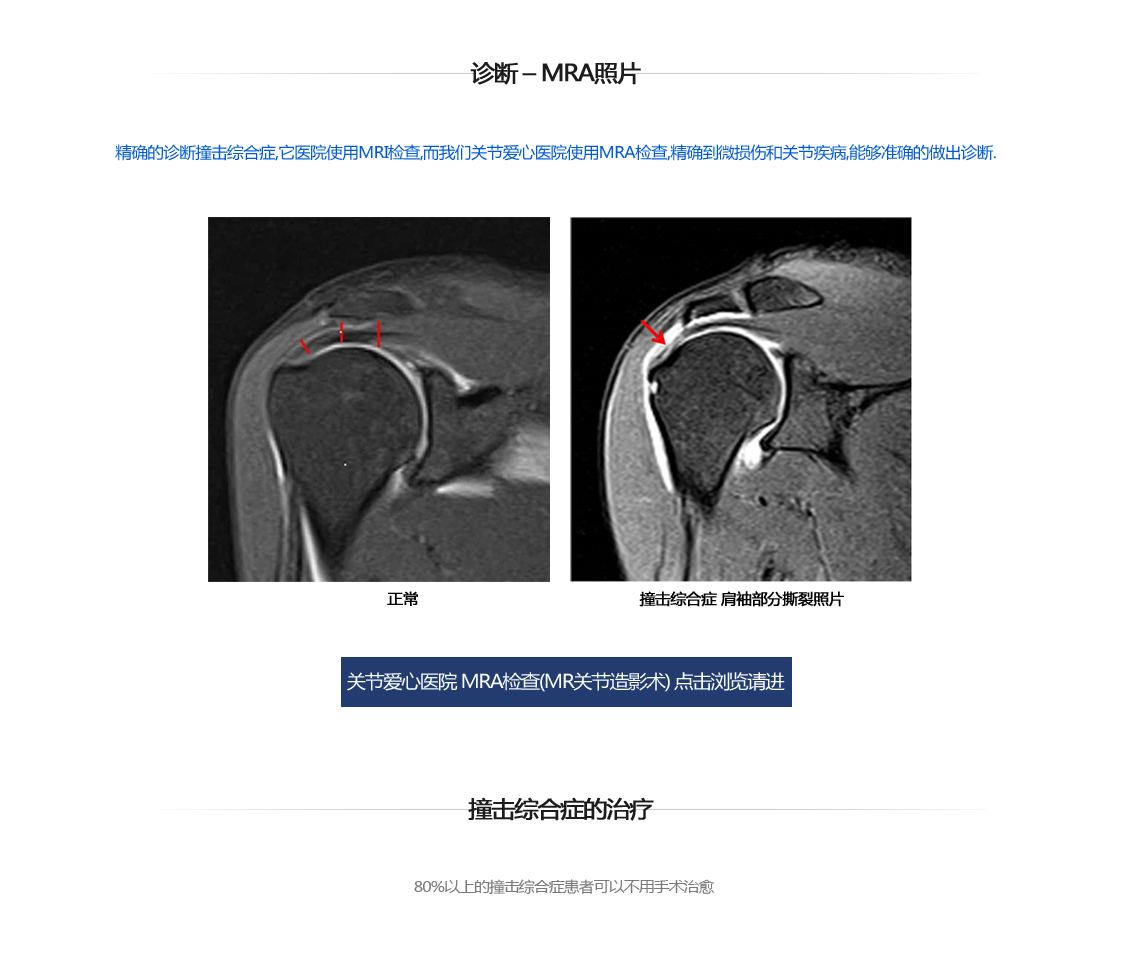

撞击综合症